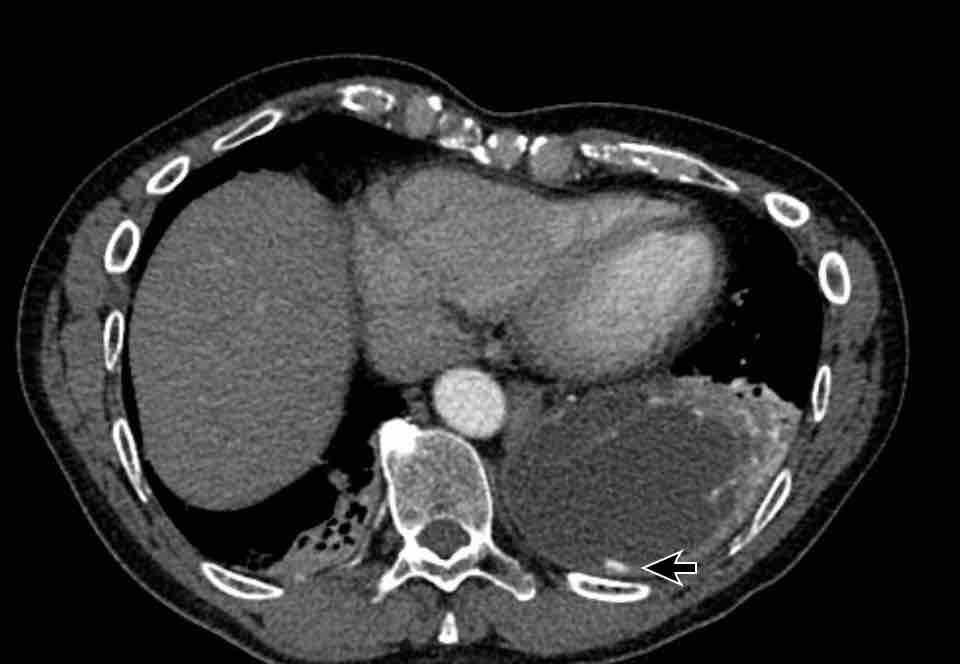

Hình ảnh

Bệnh nhân này được lên kế hoạch cắt thùy trên phải do ung thư phổi và bất thường mạch máu này ban đầu đã bị bỏ sót trên hình ảnh CT.

Những hệ quả trong phẫu thuật của bất thường như vậy nhấn mạnh tầm quan trọng của việc không bỏ sót các biến thể này.

PAPVR bên trái phát hiện tình cờ với dẫn lưu trên tim của máu từ thùy trên trái vào tĩnh mạch tay đầu trái (các mũi tên).